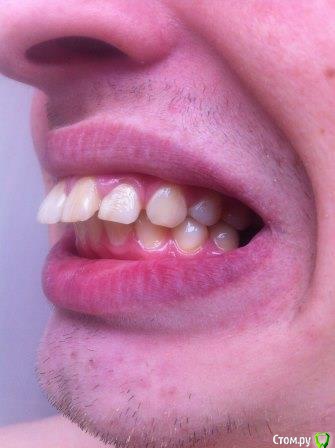

Собираюсь надеть брекеты, на консультации ортодонт сказала, что нужно удалять верхние 4ки и один нижний зуб справа (слева 6ки у меня нет). Действительно ли это необходимо? Просто все чаще натыкаюсь на случаи, когда люди потом обратно раздвигают зубы и ставят импланты. Вот КЛКТ 16x16 - https://yadi.sk/d/40q5jLjb3JUzLN

И, возможно, глупый вопрос, есть ли смысл вместо брекетов удалить верхние кривые 1ки и вставить импланты? Собственно, из-за них я и хочу брекеты поставить. Раньше такую мысль я отметал, но теперь задумался... все таки 2 зуба меньше чем 3, да и быстрее и дешевле

ТРГ нет, только КТ. Хотелось бы понять, оправдано ли удаление верхних четверок. + ко всему корни их вроде как выступают в пазуху, это тоже лишние осложнения. Был у 3х ортодонтов, один как увидел КТ предположил, что скорее всего нужно будет удалять, другой сказал что ничего не надо, что перетянем все назад и так, третий сказал что пограничный случай, в ходе лечения разберемся (правда смотрел он только панорамный снимок). Мнения очень полярные